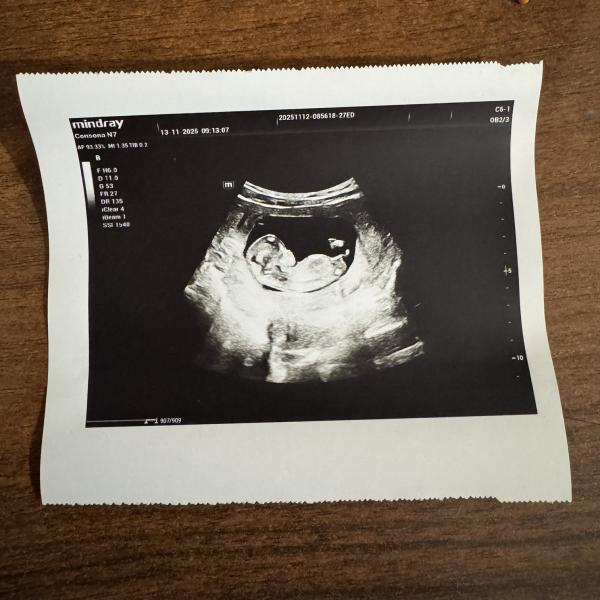

Первое фото сделано вчера, вторые 2 сегодня. Как думаете мальчик или девочка?)

Разный пол сказали на двух УЗИ😄

Вчера мне с уверенностью без «похоже» дали конверт с полом. Сегодня узистка сказала , что на первом скрининге конвертов не дает и сказала , что похоже на девочку, потом , что похоже и на мальчика и на девочку.

Сейчас я открыла вчерашний конверт, а там мальчик)